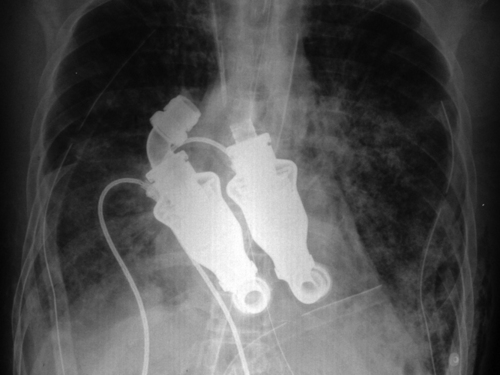

U laboratoriju Instituta za istraživanja na životinjama, živi 8-mjesečno tele imenom Abigail. Cohn i Frazier uklonili su Abigailu srce i zamijenili ga s dvije centrifugalne pumpe. Ako slušate na prsima sa stetoskopom, nećete čuti otkucaje srca, kaže Cohn. Ako ispitate arteriju, nema pulsa. Ako tele spojite na EKG, bila bi ravna crta, dodao je.

Crpke pogone krv Abigail i pomiču je kroz tijelo. Po svakom mjerilu za analiziranje bolesnika, Abigail nije živa. Ali, ovdje možete vidjeti da je ona snažno, veselo, razigrano tele koje mi liže ruku, kazao je Cohn.

U ožujku, nakon što su napravu ispitali na 38 teladi, Cohn i Frazier iskušali su svoju napravu na ljudskom srcu. Izabrali su Craiga Lewisa, 55-godišnjaka, koji je umirao od amiloidoze, rijetke bolesti koju uzrokuje nakupljanje abnormalnih proteina. Lewis je bio prvi pacijent kojemu se ugradilo umjetno srce. Prije nego je podvrgnut operaciji, liječnici su mu davali 12 sati života. Lewis je živio više od mjesec dana sa srcem bez pulsa. Umro je u travnju, zbog osnovne bolesti, a njegovi liječnici kažu da su pumpe radile besprijekorno. (Hina/jk)